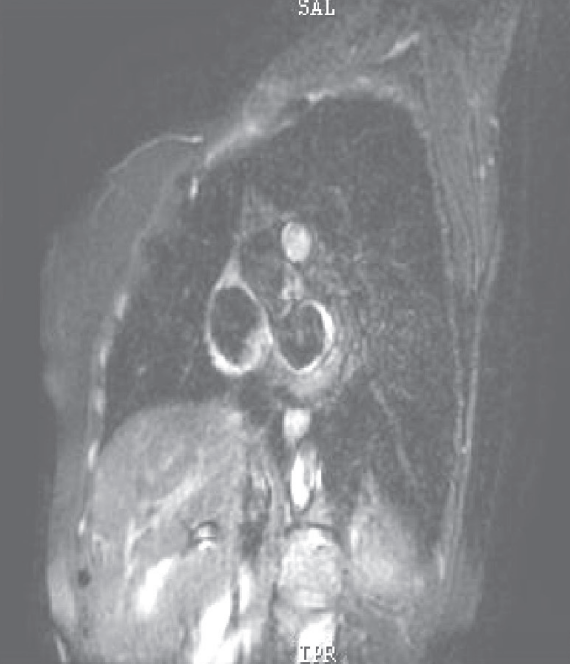

先后予葡萄糖酸钙、乳酸钙(6000 mg/d)、骨化三醇(0.5μg/d)治疗,低钙血症逐渐纠正,1个月后LVEF恢复至30%,NYHA心功能II级。继续补钙治疗,1年后调整每日用药为“乳酸钙3g、α-钙剂2μg、卡维地洛12.5 mg、左甲状腺素150μg”,复查心脏超声,左心室舒张末期内径47 mm,左心室收缩末期内径33mm,LVEF 58%(图5)。

图5 复查心脏超声